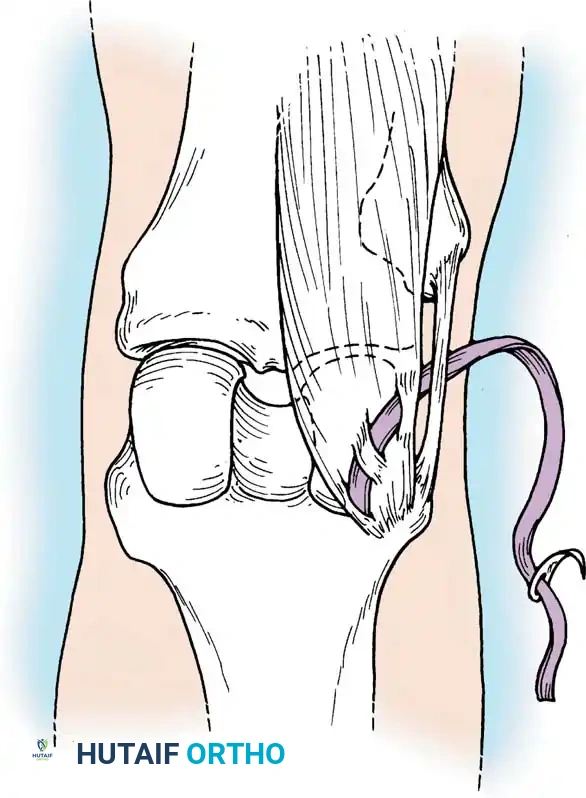

3. Diagnostic Arthroscopy and Intercondylar Notch Preparation

Standard anterolateral (viewing) and anteromedial (working) portals are established. A comprehensive diagnostic sweep is performed, addressing any meniscal or chondral pathology. The ruptured ACL stump is debrided, preserving the tibial footprint to aid in anatomic tunnel placement and preserve mechanoreceptors.

If notch stenosis is present, a limited notchplasty is performed using a motorized burr to prevent graft impingement in full extension.